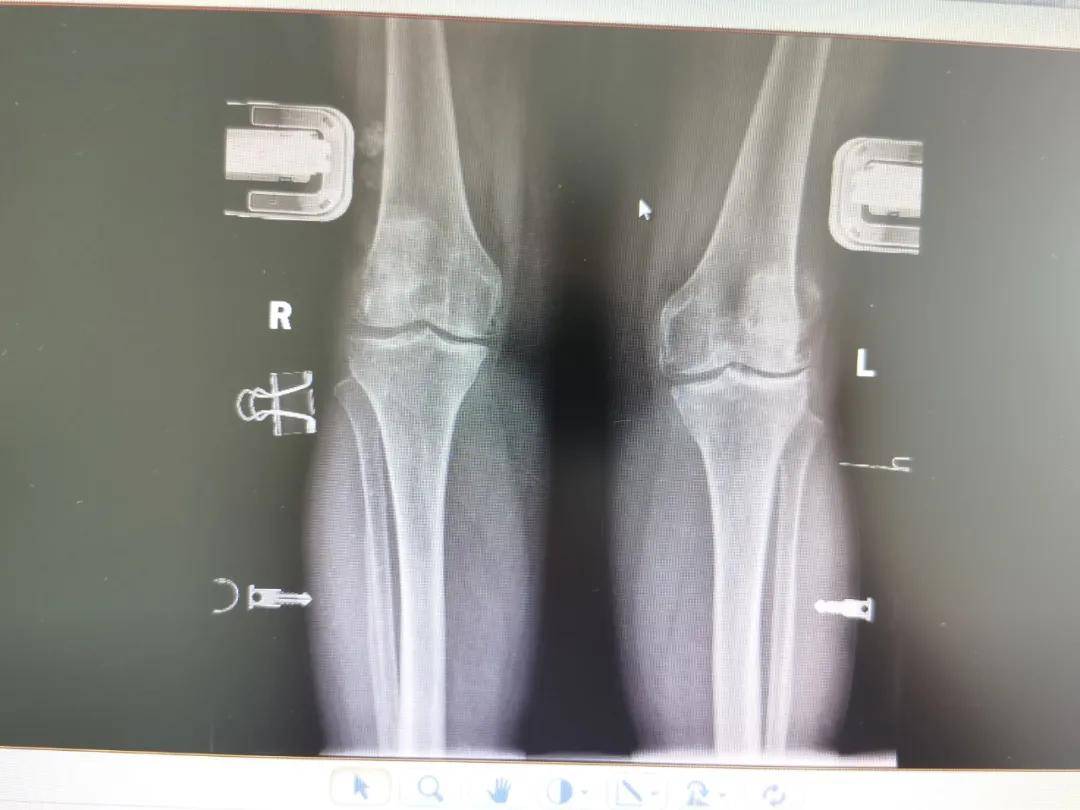

膝骨关节病合并膝外翻畸形,九江市中医医院为其成功实施全膝关节置换术